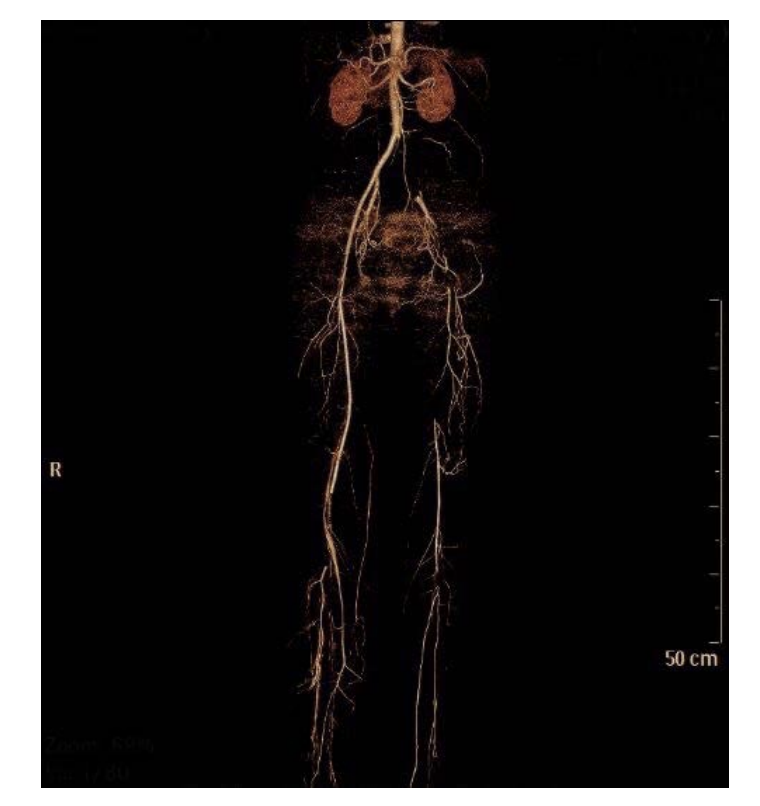

A 46-year-old female patient presented to the emergency unit with clinical symptoms and signs of left acute lower limb ischemia. The patient had no risk factors for atherosclerosis like diabetes mellitus, hypertension, hyperlipidemia, or smoking, and no history of coronary artery disease. Two months prior to this presentation she had a stroke with dysarthria, dysphagia, and right sided weakness that lasted for 2 days and she was started on aspirin. In the emergency room she was hemodynamically stable, and the left foot was painful, cold, pale, weak, and pulseless. The basic labs were normal, and the ECG showed no arrhythmias. She had a CT angiography which showed total occlusion of the left iliac and femoral arteries with reconstitution of blood flow to the popliteal artery (Figure 1). She was transferred to the operating room and underwent a successful thromboembolectomy with return of blood flow to the limb. Post operatively, the patient had transthoracic and transesophageal echocardiography and CT angiography of the chest, head, and neck. The echocardiography showed a patent foramen ovale and a right ventricular thrombus 2 cm in size. It also showed pulmonary hypertension with a right ventricular systolic pressure of 50 mmHg. The CT of the chest showed large, massive filling defects in the main and primary branches of both pulmonary arteries, representing massive PE (Figure 2). The CT of the head showed filling defect in the confluence of the superior sagittal sinus extending to the left transverse sinus, concerning for venous thrombosis with normal carotid and vertebral arteries. Lower limbs venous doppler was negative for deep venous thrombosis. Thrombophilia workup was negative except for reduced Antithrombin III level possibly due to heparinization.